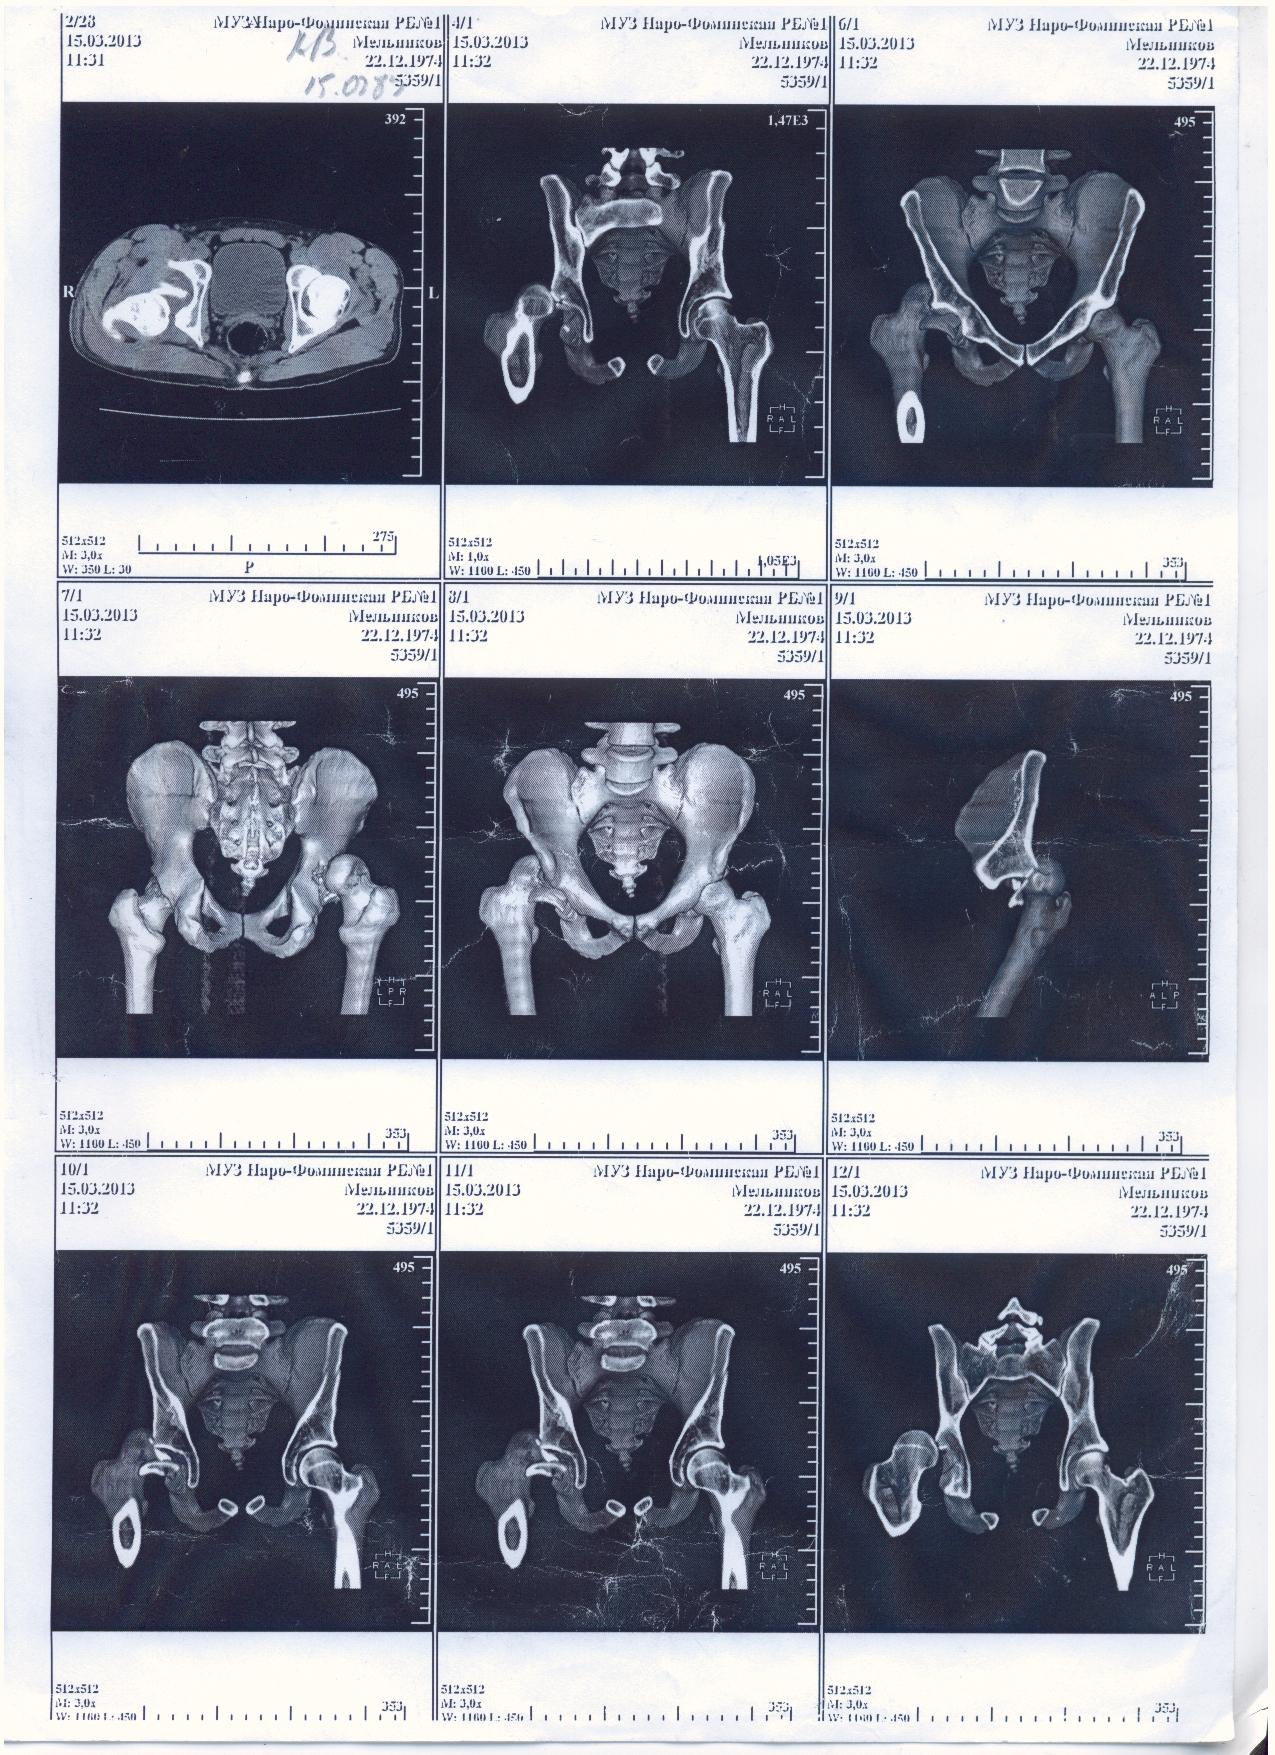

Мой товарищ попал в страшную аварию, виновник аварии как и два его пассажира погибли. Товарищ с пассажиром живы, но другу нужна сложная операция. Мы не можем никак найти врача способного прооперировать бедренный сустав, в пироговке отказали. Парню всего 30 лет всеми силами пытаемся поставить на ноги. выкладываю выписки и документы, могу выслать архивом на почту или привезти куда скажите.

Если кто то может помочь с поиском доктора или клиники буду благодарен.